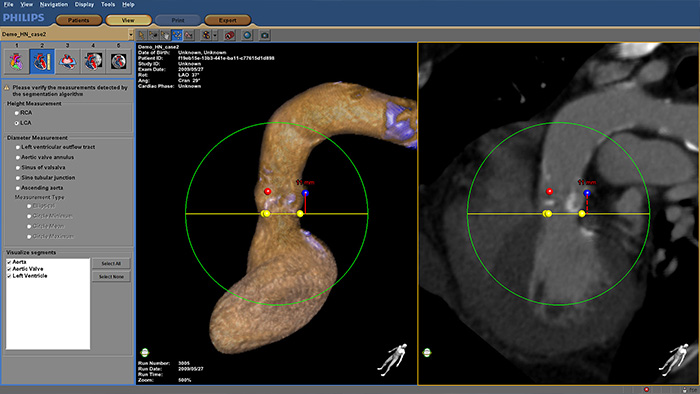

Machen Sie Transkatheter-Aortenklappen-Implantationen (TAVI) und andere anspruchsvollen Verfahren zur Behandlung organischer Herzkrankheiten zuverlässiger und einfacher. Das immersive Benutzererlebnis ist hochgradig automatisiert, um Planung, Implantatauswahl und Auswahl des Projektionswinkels zu vereinfachen. Während der Verfahren bietet HeartNavigator Live-Bildführung zur Unterstützung der Positionierung des Implantats.